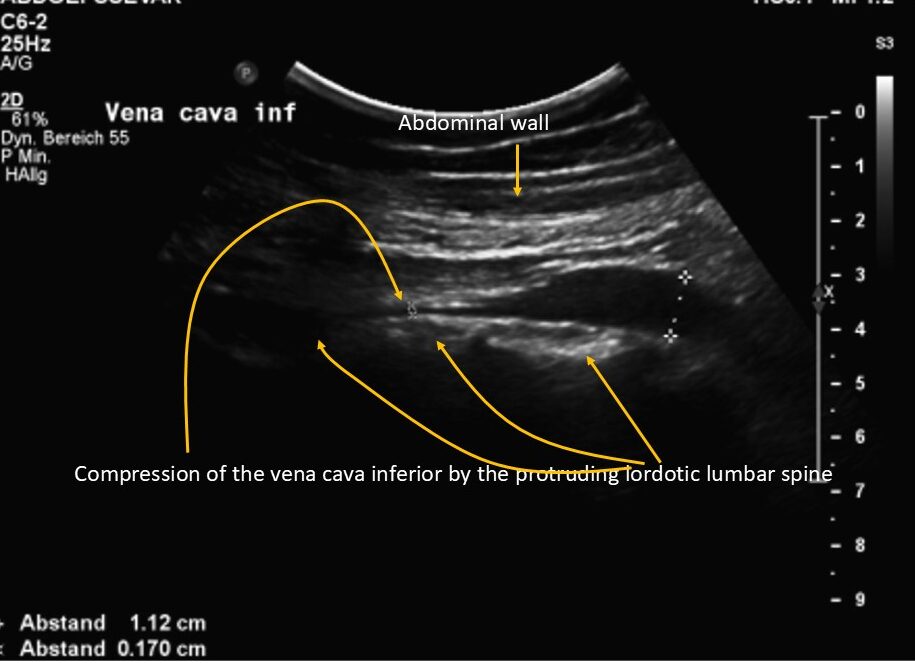

The exaggerated lumbar lordosis was compressing the inferior vena cava, which increased the backflow pressure in the left leg.